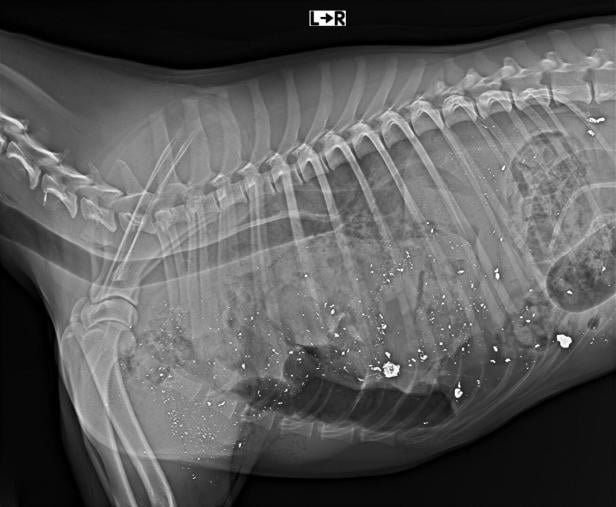

Röntgenaufnahme eines Hundekörpers

Röntgenaufnahmen zeigen die Splitter von der Kugel im Körper des Hundes.

Zurück nach Oberösterreich: Erst nach fünf Minuten soll der 84-jährige Jäger aus seinem Hochstand gekommen und den verzweifelten Pritz gefragt haben, wie er ihm zu einem neuen Hund verhelfen könne. In der Tierklinik wurde Cooper zur Beweissicherung geröntgt. Die Bilder zeigen, dass sein Körper voller Splitter der Kugel war.